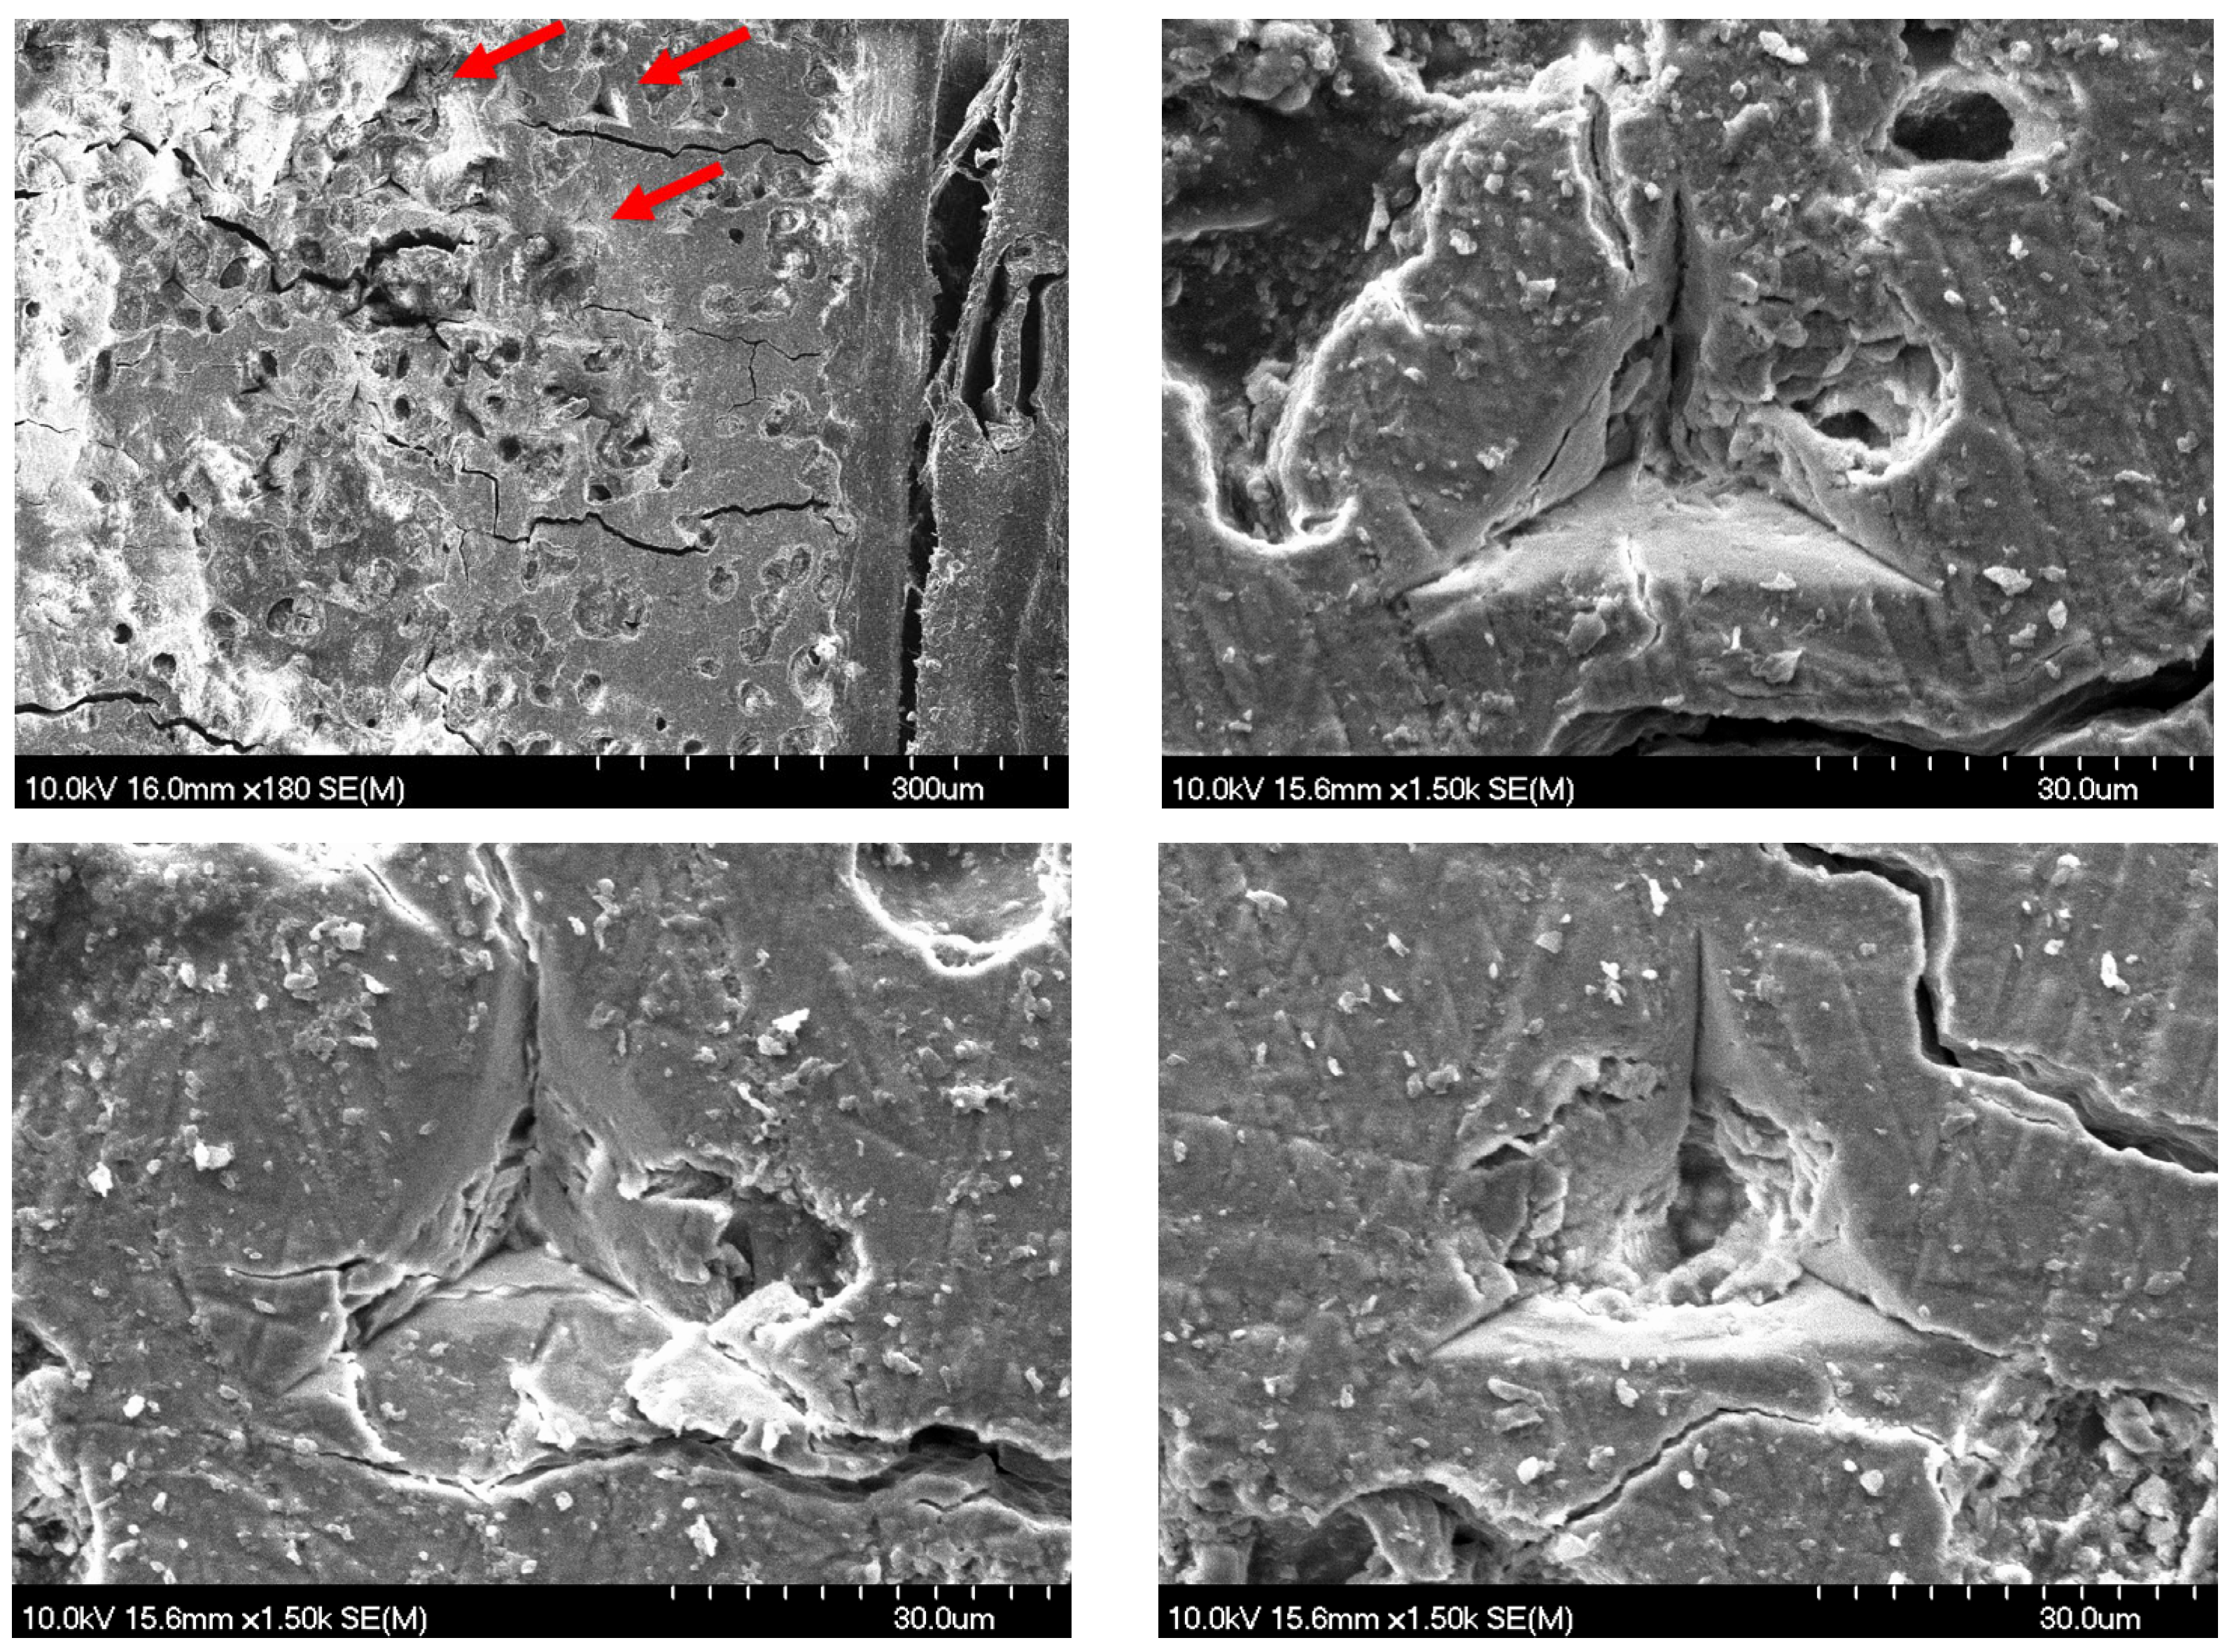

2.3. Surface Morphology and Characterization